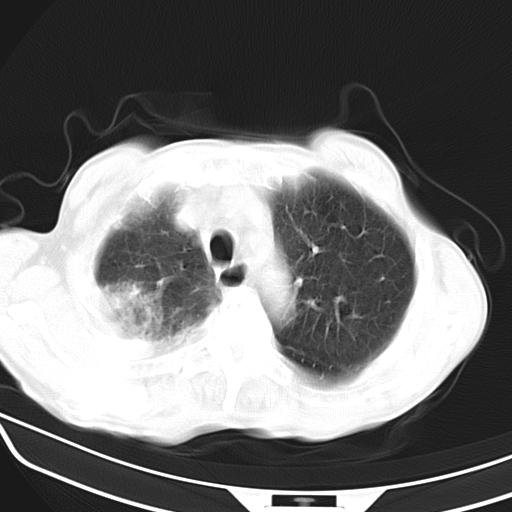

男,70,发烧咳嗽咳痰10余天,查痰结核菌阴性。否认以前有肺病史。治疗10天后症状减轻。 img]/upload/forum/2009/12/302117469692.jpg[/img]

双肺多发斑片状条索样及网格状改变,右上肺可见大个空洞,首先考虑tb慢性炎症并空洞形成。

双肺多发斑片状条索样及网格状改变,右上肺可见大个空洞,首先考虑tb慢性炎症并空洞形成。特发行纤维化。肺癌待排。

影像所见:右上肺见一巨大厚壁空洞,内壁欠光整,右上肺广泛斑片状、大片状模糊阴影。

影像所见:右上肺见一巨大厚壁空洞,并见分隔,内壁欠光整,右上肺广泛斑片状、大片状磨玻璃阴影。